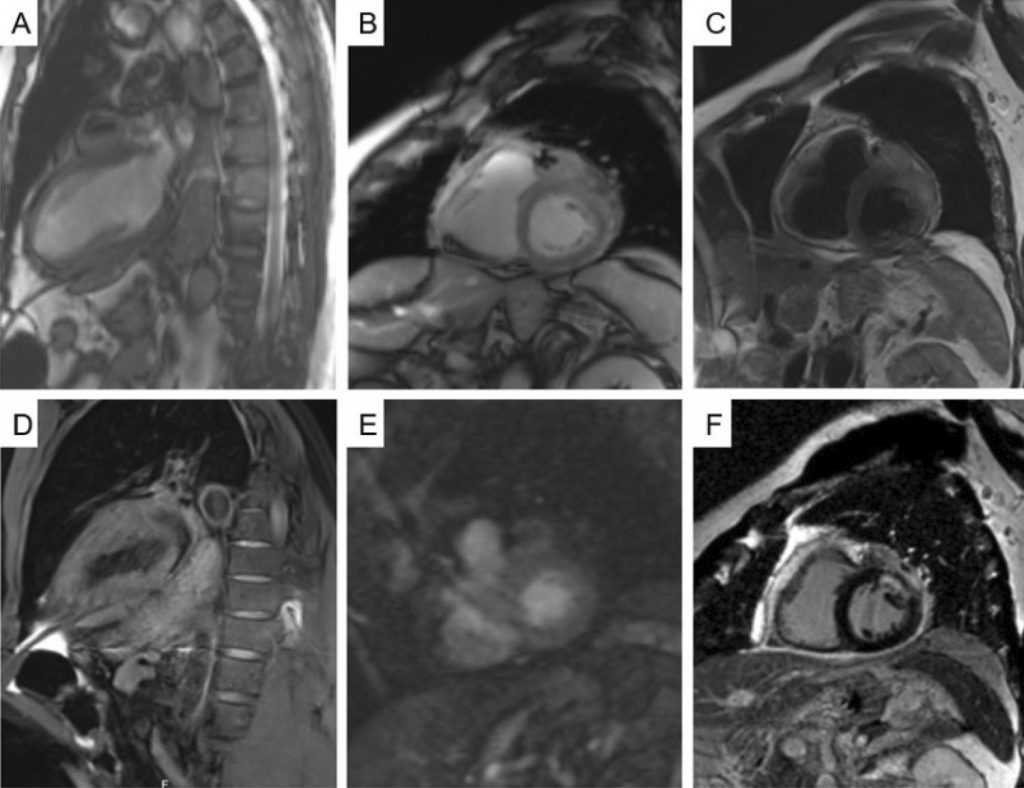

Um Caso de Doença Cardíaca Metastática Revelada após Infarto Agudo do Miocárdio e Pericardite

As metástases no coração e pericárdio são muito mais comuns que os tumores cardíacos primários e geralmente estão associadas a mau prognóstico. , Embora sejam mais frequentemente assintomáticas, as metástases cardíacas podem simular doenças cardíacas primárias, como síndromes coronárias agudas, insuficiência cardíaca congestiva e pericardite. , O câncer de pulmão é a fonte mais frequente de doença cardíaca metastática, seja por extensão direta ou por uma combinação de disseminação linfática, hematogênica e transvenosa. ,